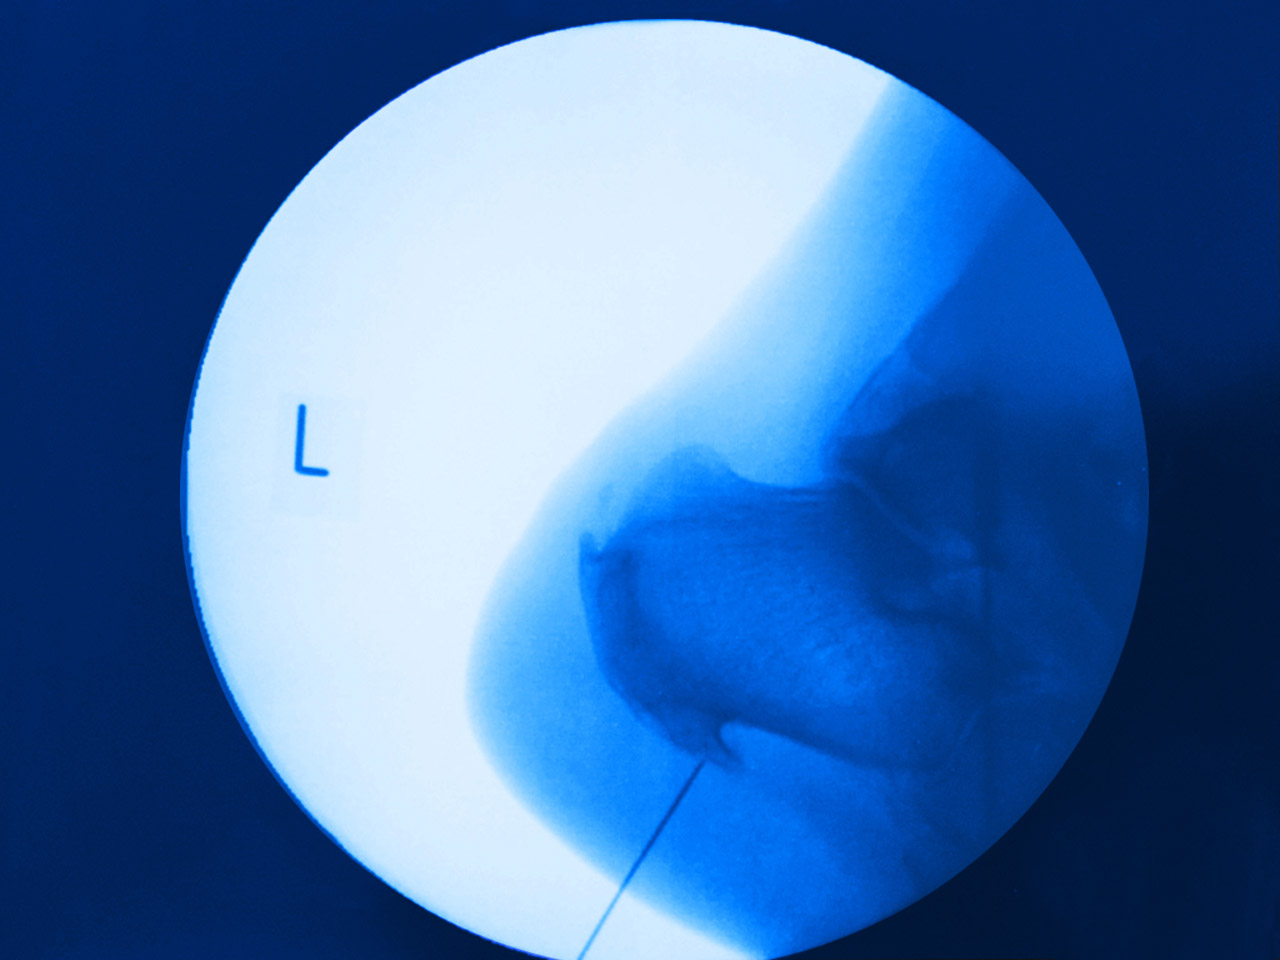

Bild 1 und 2: Behandlung des chronisch schmerzhaften Fersenbeins mit der TKS-Sonde.

Bild 3 und 4: Die Sondenspitze liegt am knöchernen Anteil des unteren Fersensporns.